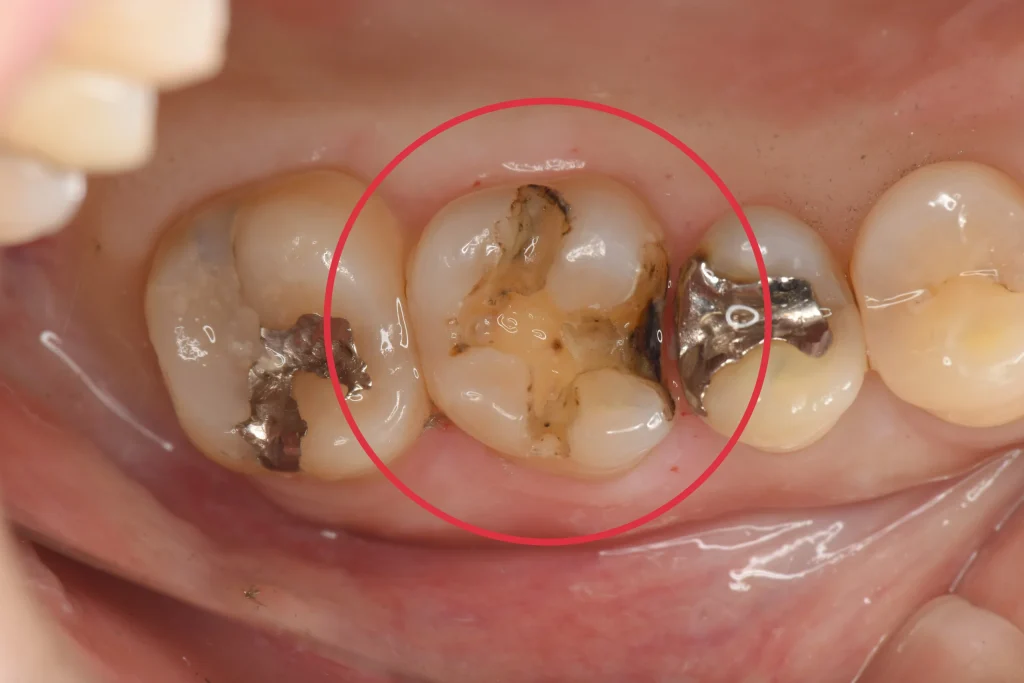

銀歯除去後、赤丸部の黒くなっている所を中心に虫歯の再発を認めます。このように保険の銀歯は虫歯の再発が非常に多い治療ですので、可能であれば再発率が低い自由診療での治療を行なっていくことが大切です。